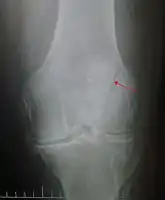

Diagnosis is based on symptoms and examination, which typically reveals a swollen knee with reduced movement and a tender kneecap.[5] A fracture is subsequently confirmed with X-rays usually taken from different angles.[3] In children an MRI may be required.[3]

The patella can break in various ways depending on the way it is injured, and into two or more pieces.[1] Types include transverse, with one fracture line and is the most common type,[5] marginal, osteochondral and the rare vertical type, or stellate, where a direct compression force gives rise to a comminuted pattern.[5][7] Patella fractures can be further classified as displaced, where the broken ends of bone do not line up correctly and separate by more than 2mm, or undisplaced and stable where pieces of bone remain in contact with each other.[1][7] If fragments of patella bone stick out from the skin it is known as an open patella fracture, and closed if the overlying skin is intact.[1]